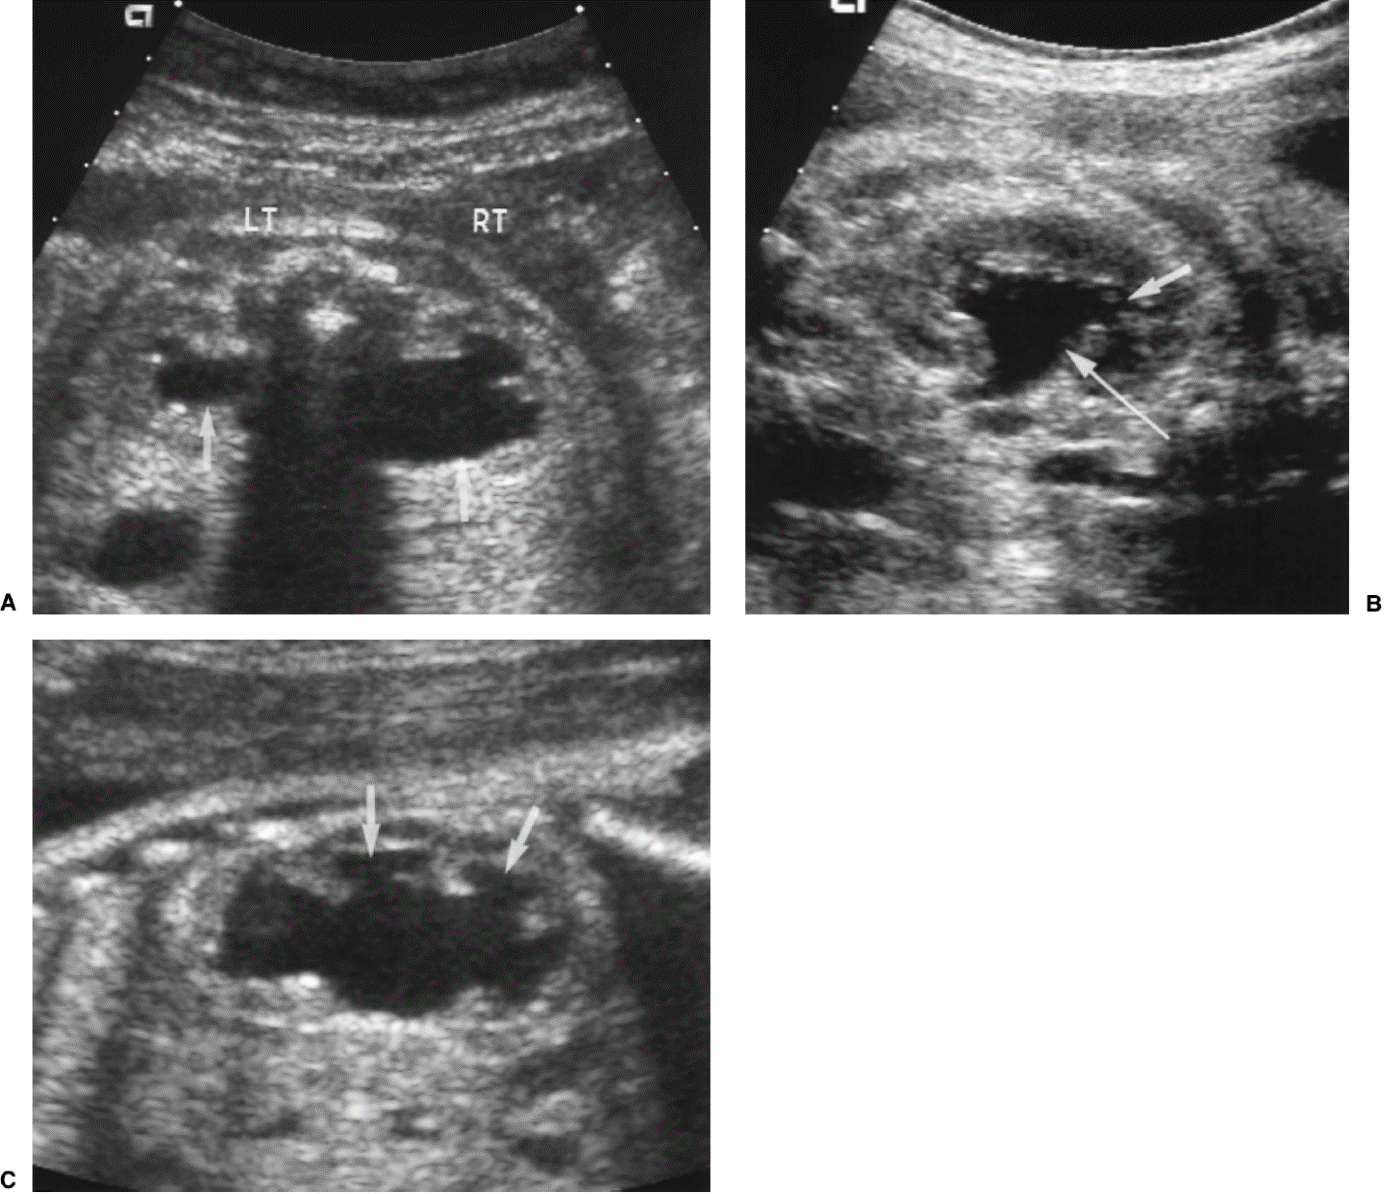

Tijdens de opname zal meerdere keren bloed worden geprikt en zullen er enkele echo’s gemaakt worden. Daarnaast zal via de katheter contrastmiddel in de blaas worden gebracht om met röntgenstraling de urinewegen af te beelden. Dit heet een mictie cystogram. De kleppen kunnen hierop niet worden gezien, maar de verwijding veroorzaakt door de kleppen, de dikke blaaswand en het eventueel terugstromen van urine naar de nieren kan in beeld worden gebracht.

Normale plasbuis voorbij de kleppen

Plaats van de urethrakleppen

Verwijd eerste deel van de plasbuis tot aan de kleppen

Kleine, kramperige blaas met kartelige contour veroorzaakt door uitstulpingen van de blaaswand (divertikels)

Terugstroom van urine tot in de nier (vesico-ureterale reflux) en verwijde urineleider

Plasfoto met contrastmiddel (mictie cystogram)